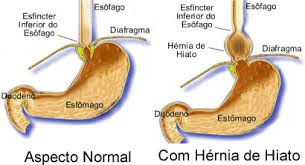

Hérnia de hiato e refluxo gastroesofágico

Hérnia de hiato é a protusão do estômago através do orifício pelo qual o esôfago atravessa o diafragma para penetrar na cavidade abdominal. Existe um músculo (músculo do esfíncter esofágico inferior) que se abre para permitir a passagem dos alimentos para o estômago e, então, se fecha para impedir que os ácidos estomacais subam para […]